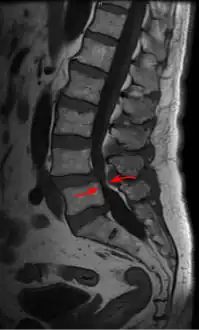

| Lumbar vertebra showing central stenosis and lateral recess stenosis. | |

MRI of a lumbar spinal stenosis L4-L5. L4-L5 antherolisthesis of grade I. Hypertrophy of interspinous ligaments in relation to Baastrup's disease. -